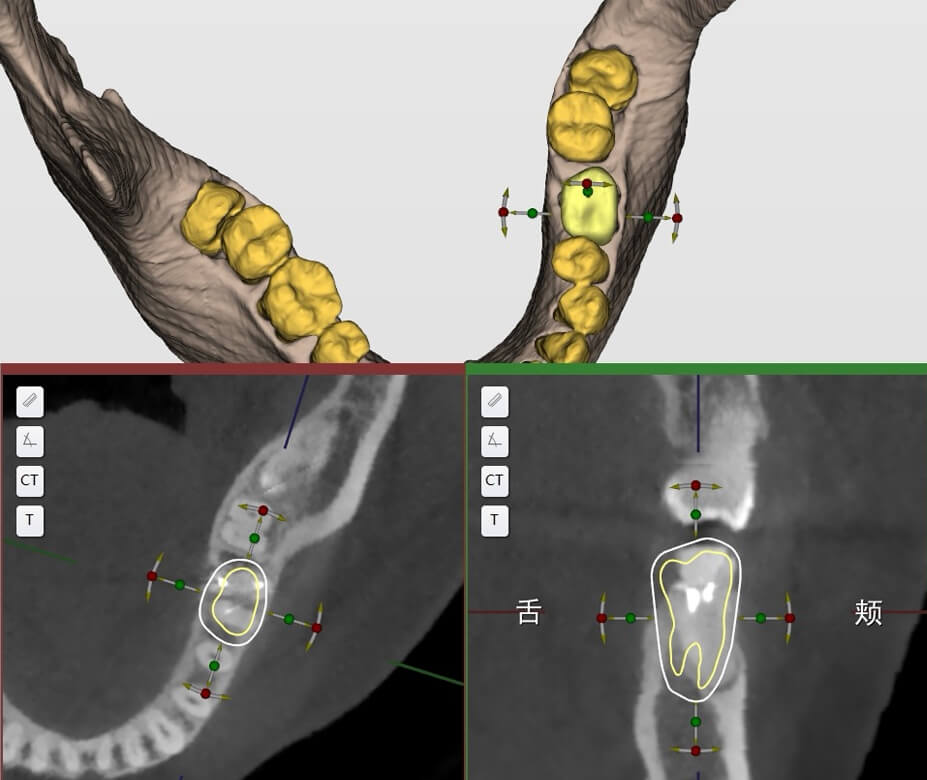

CBCT inicial + digitalização intraoral

Adaptação a diferentes dados de CBCT e digitalização intraoral; tratamento numa única visita, planeamento imediato; cirurgia no mesmo dia / prótese no mesmo dia

Registo Secundário de Pontos e Nuvem

Integração precisa entre modelos virtuais e estruturas reais